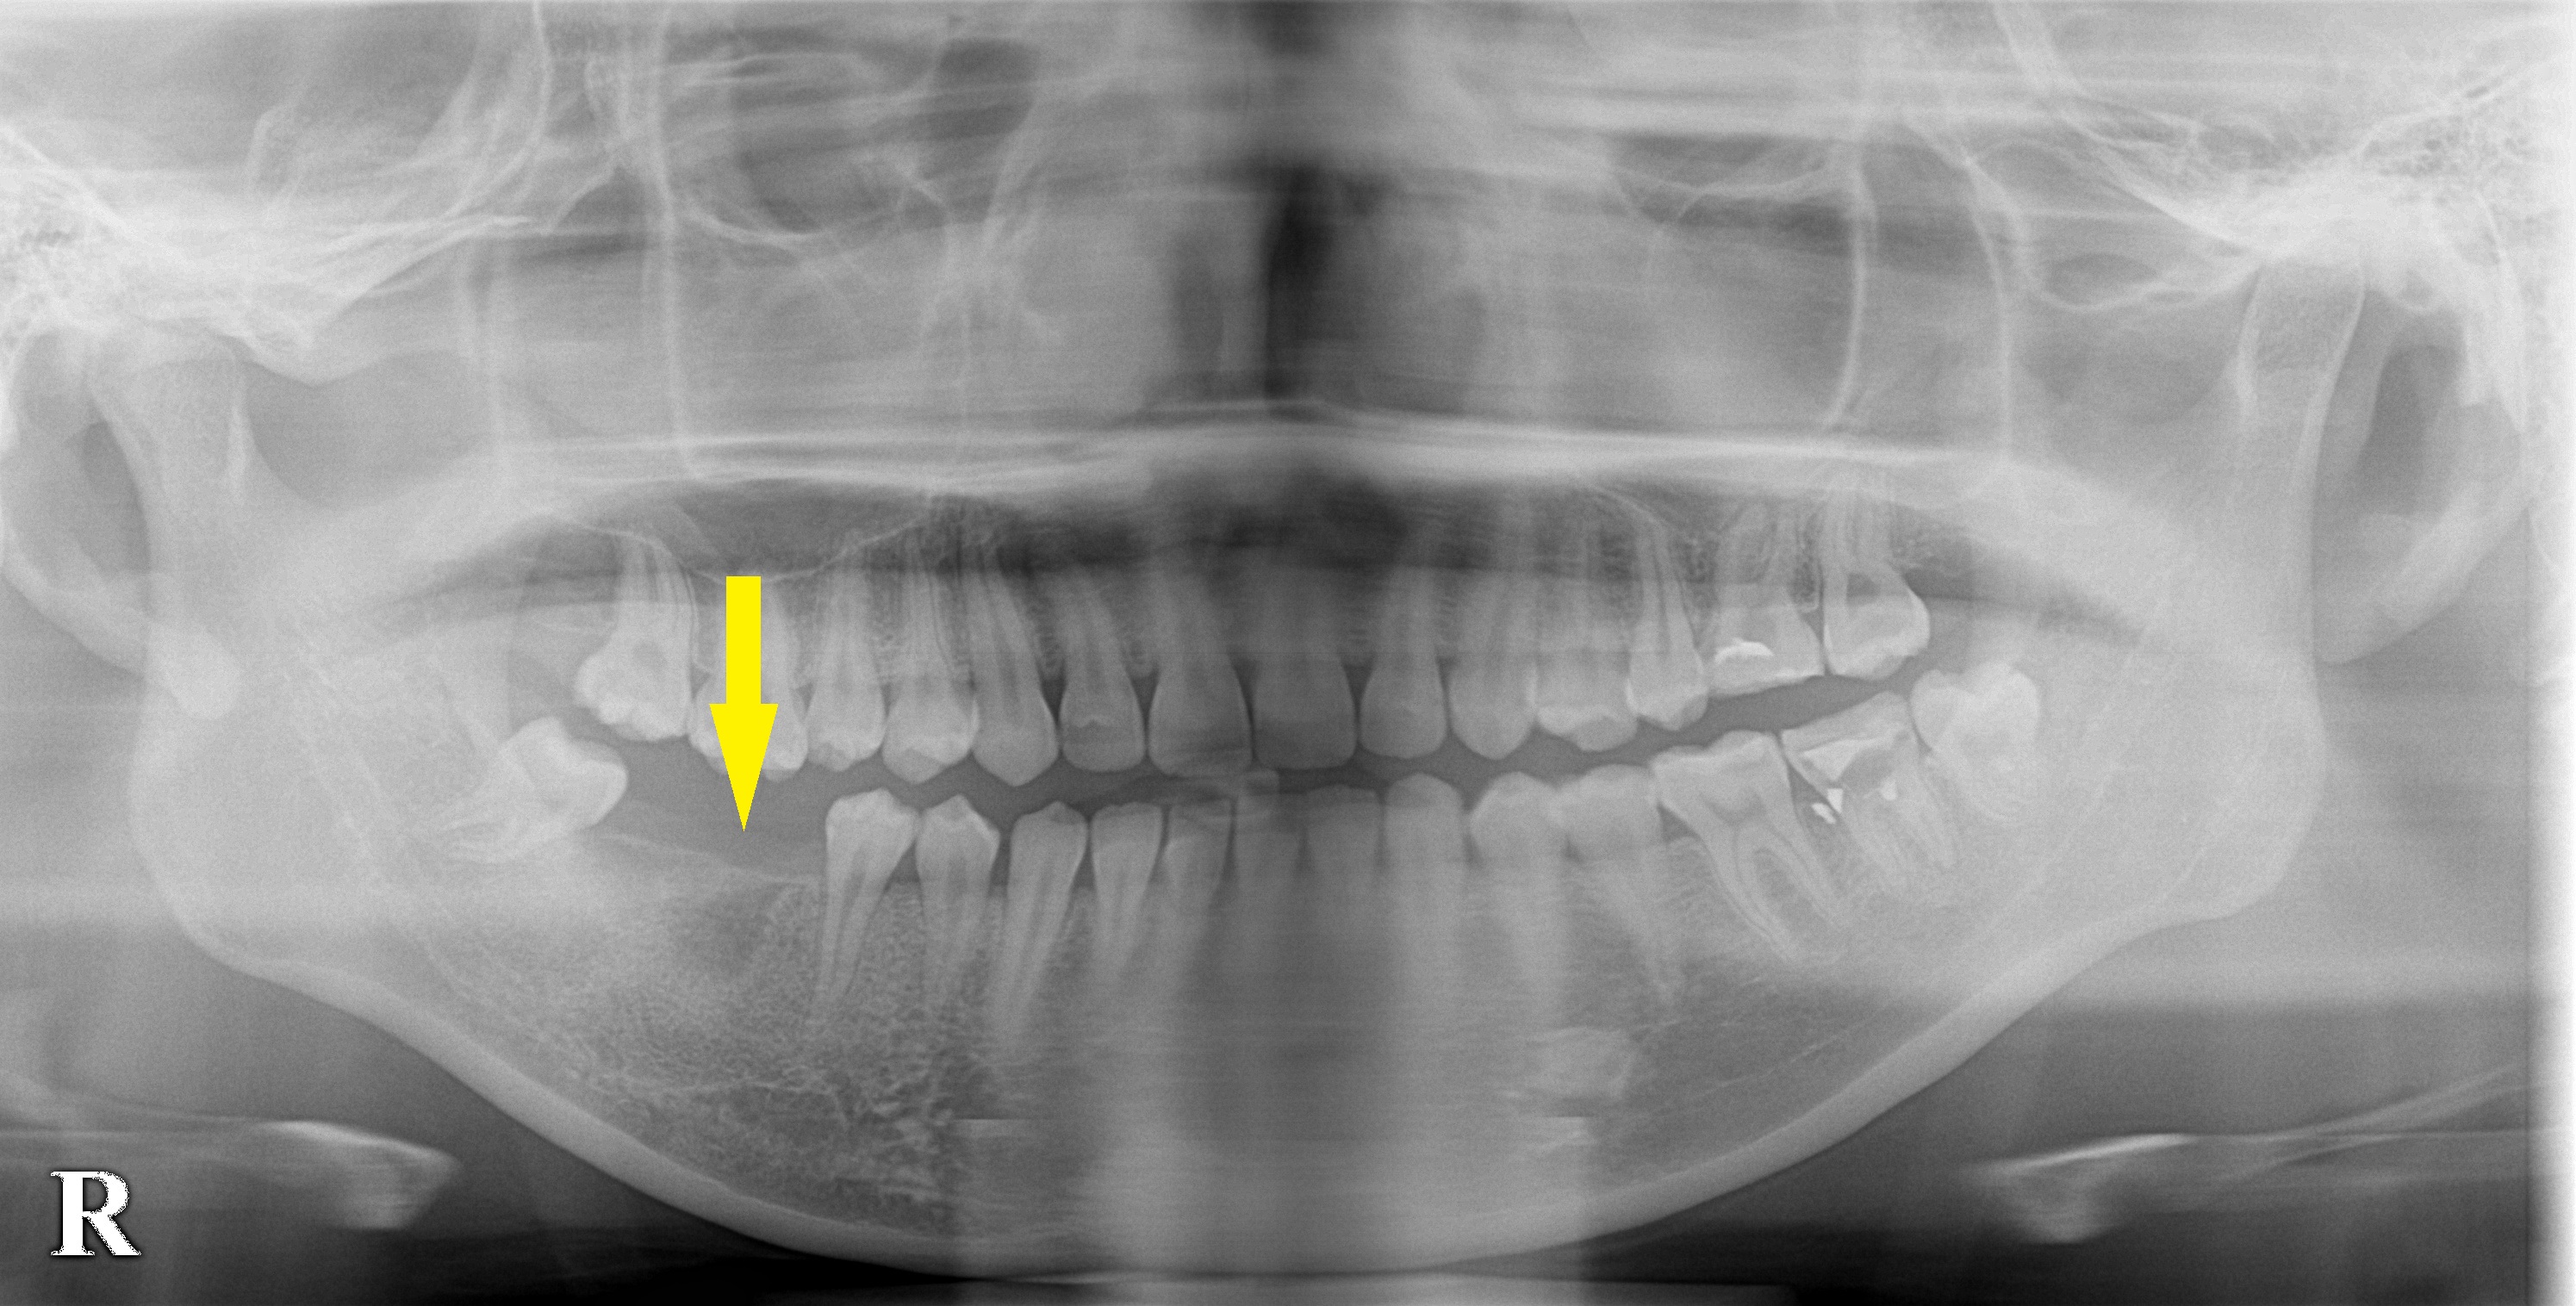

まだお若いのですが、右下顎の大臼歯の虫歯が大きく、歯が破折してしまって抜歯せざるを得なくなったそうです。

骨の量は問題なく1本だけの回復を希望されましたので、同部に本日インプラント埋入術を行いました。